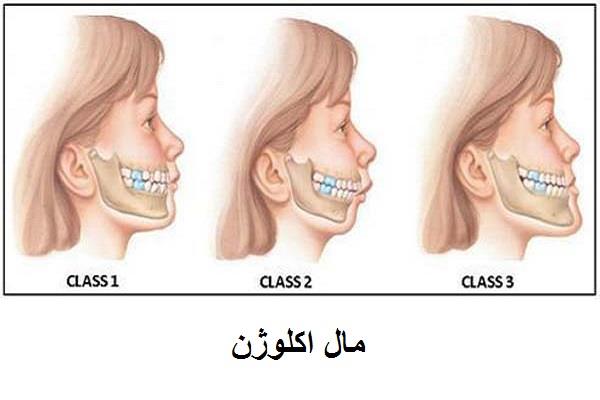

- افراد بسیار جوان با رشد فکی ناتمام

کاشت ایمپلنت در افرادی که رشد فک آن ها هنوز کامل نشده (معمولاً زیر ۱۸-۲۰ سال) توصیه نمی شود، زیرا ایمپلنت با استخوان جوش می خورد و با رشد فک جابجا نمی شود، که منجر به ناهماهنگی در آینده می شود. سن مناسب برای انجام ایمپلنت معمولاً پس از توقف رشد فک است. - ملاحظات خاص در افراد مسن و سلامت عمومی